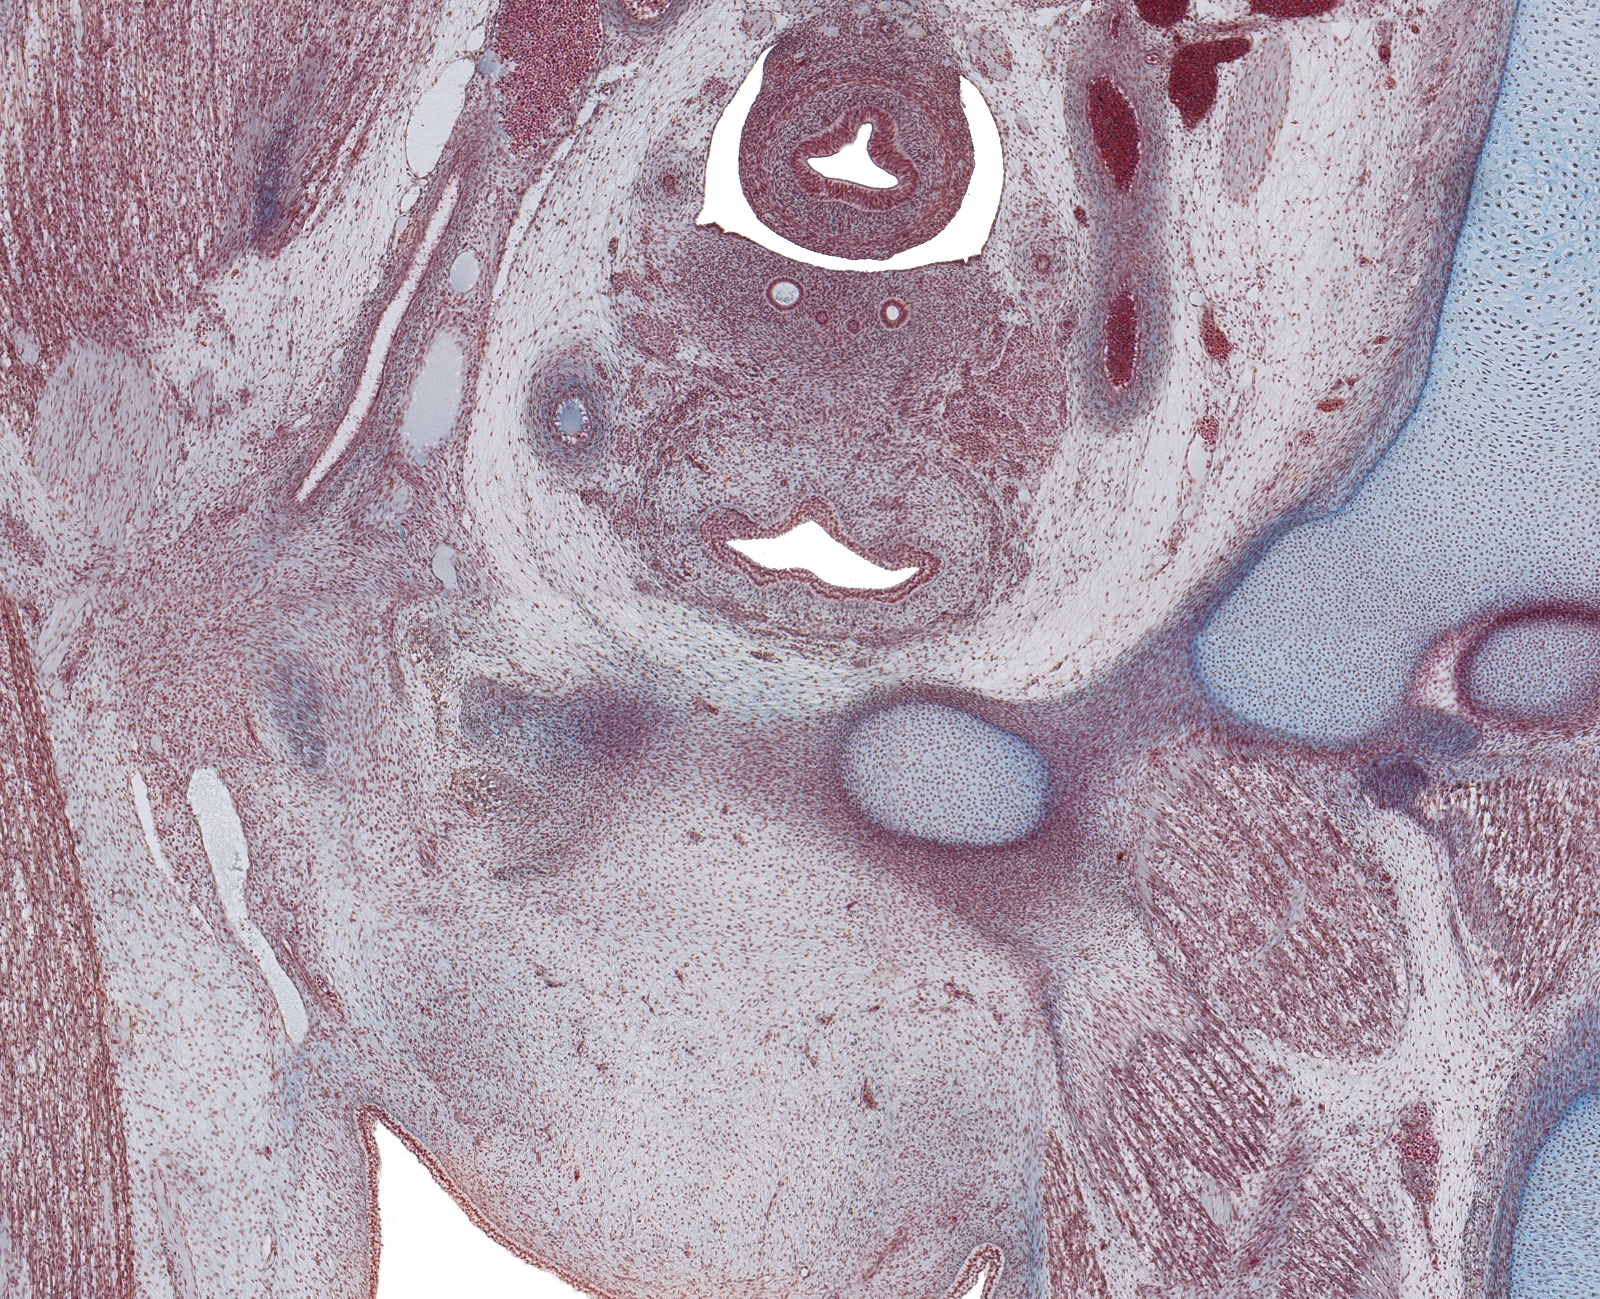

Tissue

Paramesenephric Ducts, and Gubernaculum Testis in Scrotal Fold

Carnegie Embryo #9226

193-01-01